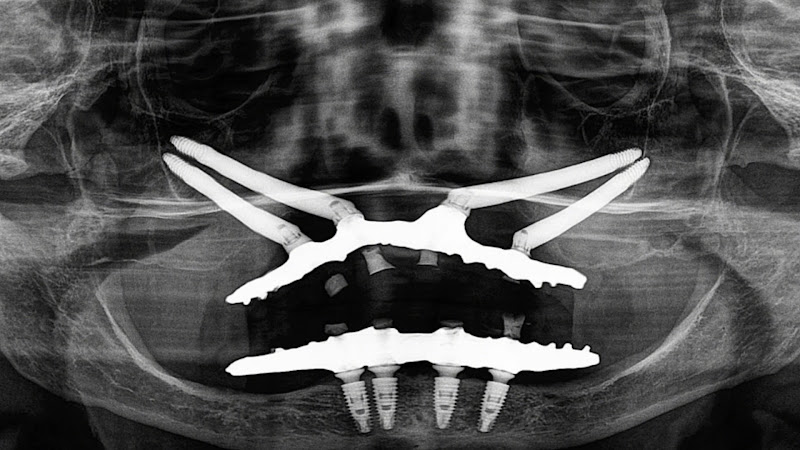

Dr. Maxuel Oliveira / Implantes Dentários / Implantes Zigomáticos / Extrações Complexas / Rio Verde Goiás